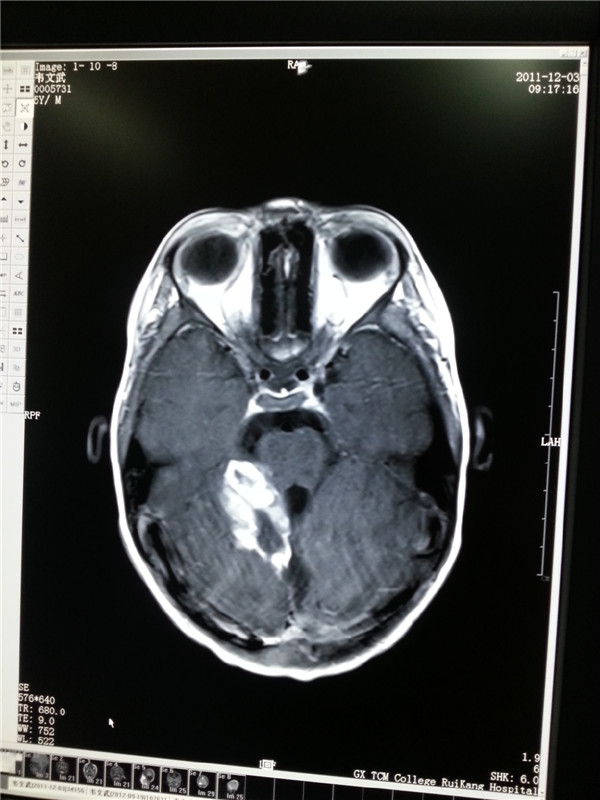

2011年5岁患儿脑胶质瘤接受射波刀治疗

2011治疗前白点为3×2×2肿瘤(左图);2012复查肿瘤明显缩小(右图)